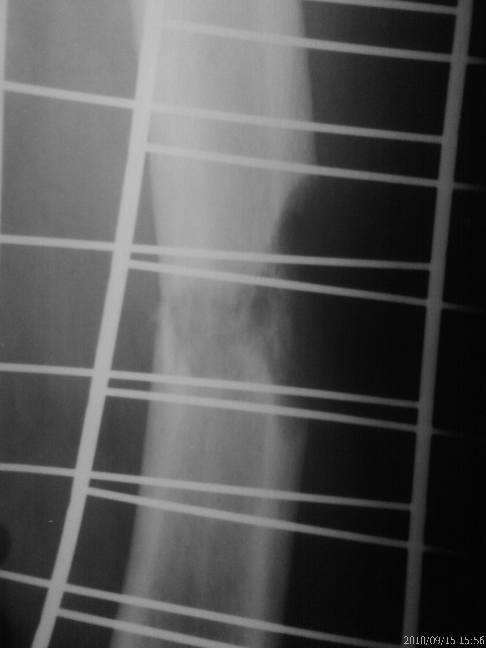

2 недели назад пациент поскользнулся, сломал бедро. 4 месяца назад проведена

нефроэктомия по поводу опухоли почки. На рг патологический перелом бедра. От

наложения гипсовой повязки отказывается настаивает на оперативном лечении.

Интрамедуллярный остеосинтез блокирующими гвоздями нет возможности провести.

Планируем остеосинтез пластиной LCP винтами.

Проводить резекцию кости? Какой обьем резекции?